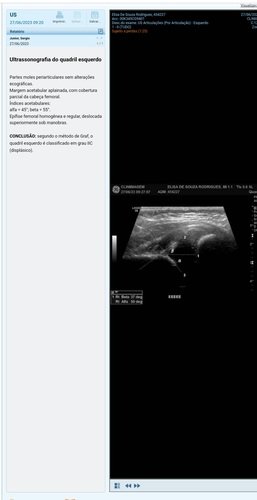

Estes são meus últimos raio x,bem rescentes .